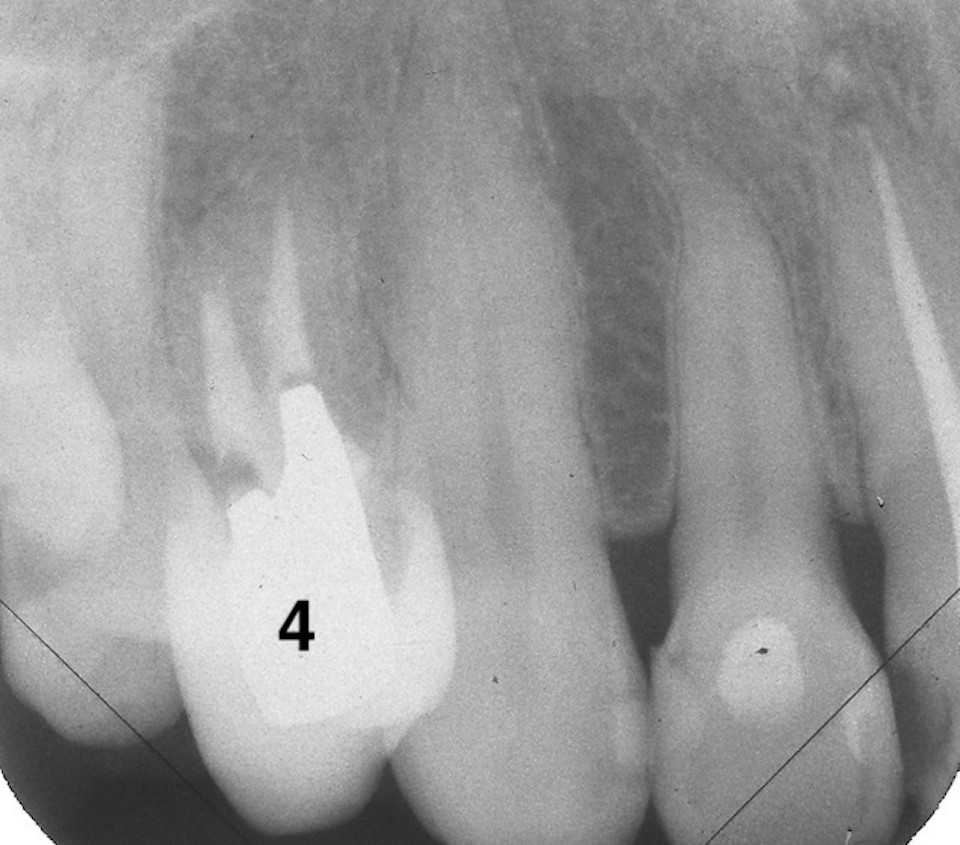

30代女性、右下7、Per、歯牙破折、歯根吸収?ほとんど抜けそうな(抜けている)状態で来られた。ご本人にお訊きしてもどうしてこうなったのか記憶にないそうだ。とりあえずレントゲン写真でのbefore/afterだが、近心の歯根が半分無くなっている。吸収されたのか、破折して破折片がどこかに行ってしまったのか、よく分からない。とりあえず抜いてみるしかない。beforeafter処置前はセラミック系の冠が装着されていたが、グラグラしている。冠は横から切断して除去した。歯根は前後(近遠心的)に破断していてグラグラしているのを確認した。どこまで健全歯質が残っているか軟化象牙質を削除しながら見てみたが、切削バーが届く範囲で健全歯質を確保するのはできなかった。抜歯してみないと正確なところは分からない。抜歯して直視下で見ないと軟化象牙質を除去し、健全歯質を出すことはできない。健全歯質の新鮮面を出さないとスーパーボンドは接着しないので、歯根の再建はできないということになる。抜歯再植は次回にすることにしてα-TCPで仮封鎖した。つづく

30代女性、右下7、Per、歯牙破折、歯根吸収?https://plaza.rakuten.co.jp/mabo400dc/diary/202509180000/抜いてみると複雑な欠損状態で、頬側の上の部分は歯根膜、骨膜等の細胞が少なかったので、生着しにくく使えないと判断した。頬側の部分に欠損がある。欠けたのか吸収されたのか分からない。吸収だとすれば自身の免疫系が自身の歯を異物と見做しての排除機転が働いているということなので、生着したとしても排除機転は止まらないだろう。舌側は歯根膜は残っている。頬側は80%の歯根面が失われている。歯根膜がないので生着しても歯槽骨はできない。強い咬合力には耐えられないだろう。綺麗にして接着剤が効くように歯質の新鮮面を出す。白いのはCR系のコア材。ピンク色は根管充填材。根尖付近は歯根膜が失われている。膿瘍があったことが分かる。根管充填材も除去して根尖口まで貫通させるここから歯根の折損部をスーパーボンドとCRで修復・再建していく過程。既成のポストを当ててみた。裏面(舌側)、歯根膜はほとんど残っている。内側だけで持たせている状況。上半分は歯根膜が無いので使えないと判断した。エッチング処理をしてスーパーボンドで修復根尖口も筆積み法で塞ぐCRも使い始める。舌側面CRで上半分を覆う次回は再植過程。つづく

40台女性、左下6、Per+GA、外傷性クラックGAができていたので歯髄を開けて見たのだが、歯髄は完全に失活していた。クラックがあったので3MIX+α-TCPで根管充填したが、GAは消えなかった。やはりクラックが深部まで進んでいるのか?前回のつづきhttps://plaza.rakuten.co.jp/mabo400dc/diary/202509090000/今日は抜歯して問題点を調べるまで。前後の歯根はアンダーカットになっているので、分割抜歯するしかない。なるべく歯根表面の歯根膜を損傷しないように抜くのは難しい。膿瘍は鋭匙ピンセットで掻爬・除去する。3MIX添加生食水で洗浄どうですかね。。近心根には明らかな側枝やクラックは見えません。遠心根にはクラックがあるが、根尖までは達していない。

40台女性、左下6、Per、外傷性クラックGAができていたので歯髄を開けて見たのだが、クラックがあったので3MIX+α-TCPで根管充填したが、GAは消えなかった。やはりクラックが深部まで進んでいるのか?これ以上の打つ手がないので抜歯再植を試みた。抜歯も分割抜歯だったがまだ病状が進んでいないので骨植もよかったので、かなり時間もかかり難しかった。結局クラックは遠心根だけで近心根には見えなかったので、側枝があるのかもしれないが、近心のGAの原因はよく分からなかった。どうなるのか、経過観察が必要だ。とりあえずレントゲン写真でのbefore/afterbeforeafter